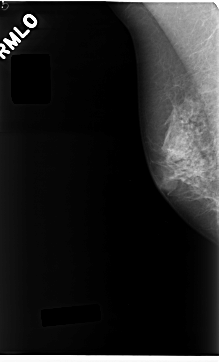

C_0237_1.RIGHT_MLO

RIGHT_CC LINES 4720 PIXELS_PER_LINE 2720 BITS_PER_PIXEL 12 RESOLUTION 50 NON_OVERLAY

RIGHT_MLO LINES 4704 PIXELS_PER_LINE 2840 BITS_PER_PIXEL 12 RESOLUTION 50 NON_OVERLAY